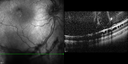

This pleasant 8-year-old child was seen in the office on March 8, 2012. He was examined for glasses and dilated examination showed retinal abnormalities.

VISUAL ACUITY: OD 20/40, OS 20/50. IOP: 12 OU. His lenses are clear.

OD: Vertical C/D ratio is 0.2. There are foveal cysts. There is also a retinal elevation inferiorly and there are patchy peripheral retinal hemorrhages.

OS: Vertical C/D ratio is 0.2. There are foveal cysts. There is peripheral retinal issues with some hemorrhage in some areas of peripheral retinoschisis.

SPECTRALIS-SD-OCT SCAN: The OCT scan does show foveal retinoschisis in both eyes. The average thickness of the macula in the right eye being 420 microns and the cysts appear to be forming predominately in the inner nuclear and inner plexiform layer. In the left eye the OCT scan shows an average central foveal thickness of 414 microns and the cysts in that eye are forming mostly in the inner plexiform inner nuclear layer. The peripheral line scans also show peripheral retinoschisis in both eyes outside the macula. It is a little bit closer in the right eye where the hemorrhage is and you can see vitreoretinal traction at the edge of the schisis cavity. (NOTE: Retinal thickness measured with Spectralis OCT is approximately 70 μm greater than that measured with Stratus OCT. This increased measurement corresponds to the inclusion of the outer segment-RPE-Bruch's membrane complex by Spectralis OCT.)